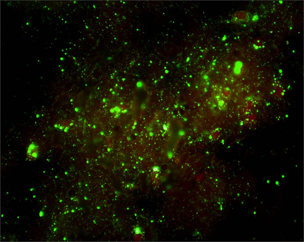

Direct fluorescent antibody (DFA) test

The DFA test demonstrates that animals with rabies have rabies virus- expressed proteins (antigens) in their tissues.

- Brain tissues are ideal for this test because rabies is present in nervous tissue (and not blood like many other viruses).

- Other innervated tissues may have antigens, but these tissues are less accurate at detecting rabies when compared to brain tissues.

- The most important part of a DFA test is fluorescently labeled anti-rabies antibody.

- When the labeled antibody is incubated with rabies-suspect brain tissue, it will bind to rabies antigen.

- Unbound antibodies can be washed away and areas where antigen is present can be visualized as fluorescent-apple-green areas using a fluorescence microscope.

- If rabies virus is absent, there will be no staining.

The DFA test has high sensitivity and specificity for detecting rabies and has been rigorously evaluated by international, national, and state health laboratories.